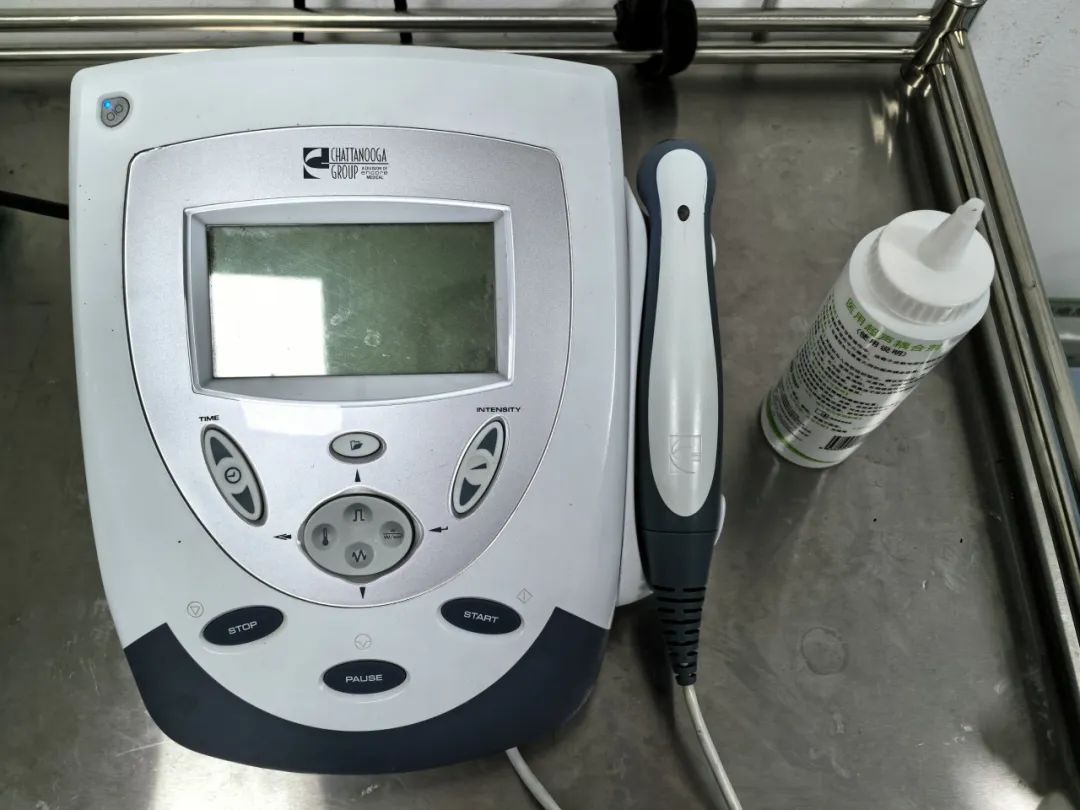

第一步,关节区的理疗,以缓解疼痛,首先在中医理疗科进行——超声波治疗、脉冲电治疗、激光治疗、推拿治疗等。